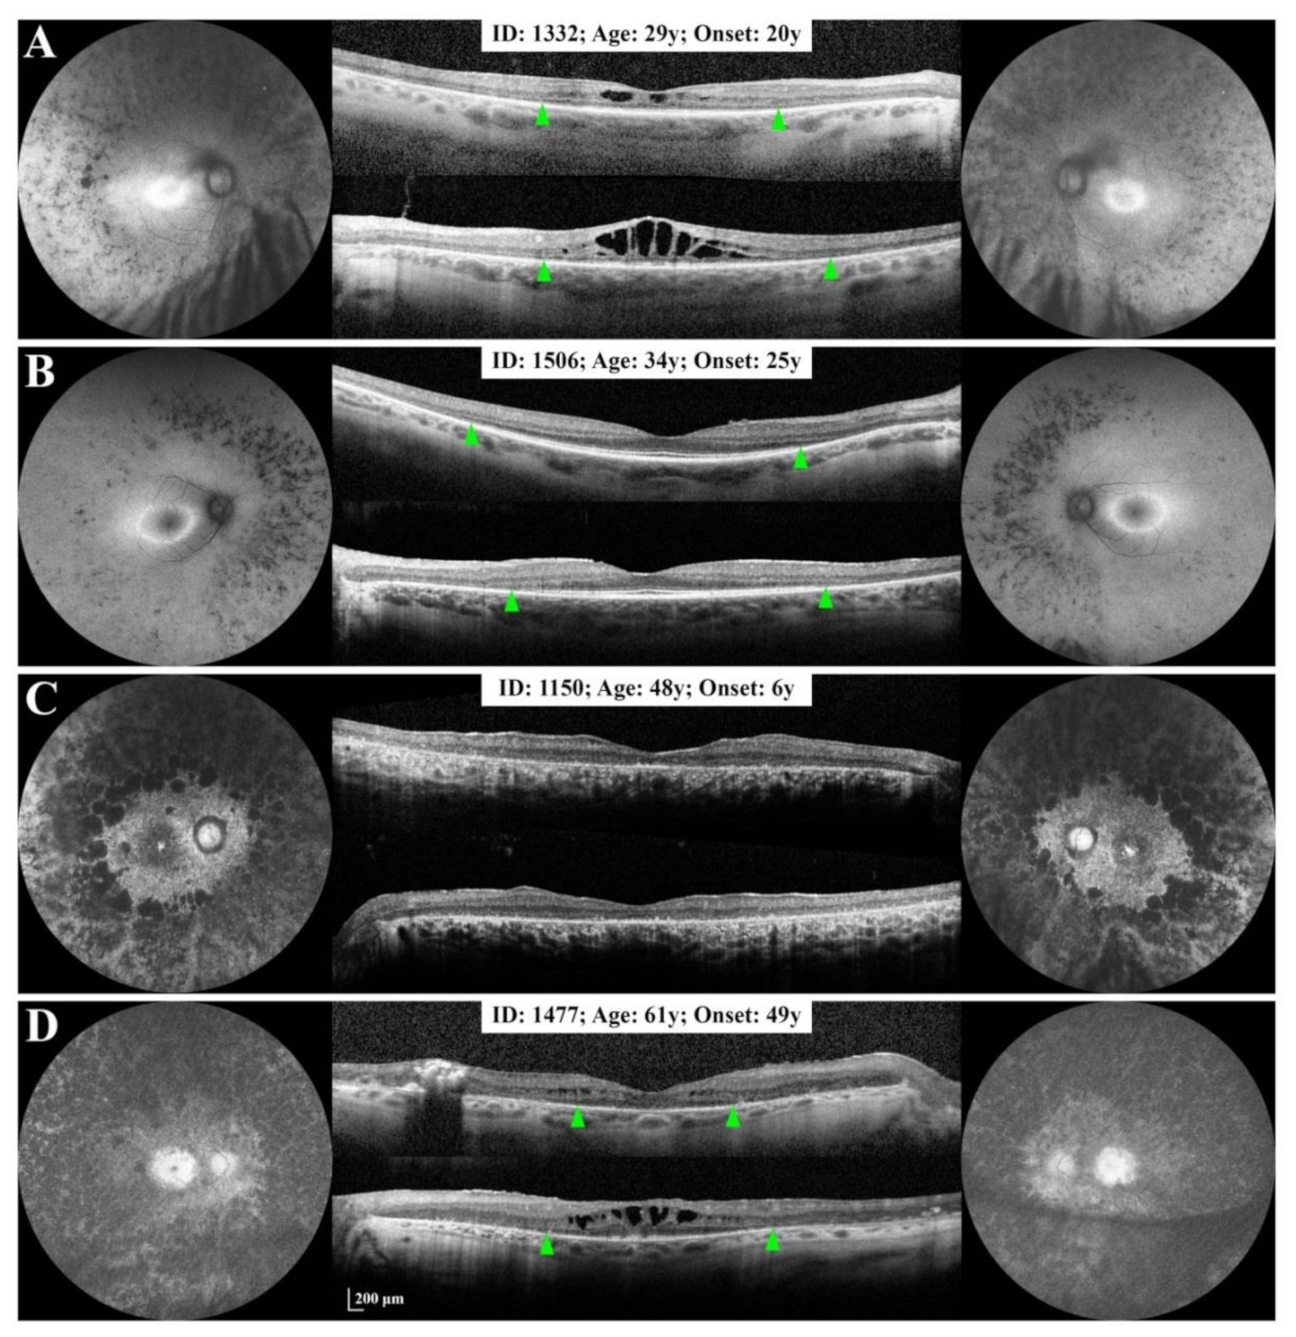

3.2.1. Small Deletion/Deletion-Insertion

| 0255 | 1332 | 29 | F | 20 | 68 (20/50) | 68 (20/50) | PSCC + | PSCC + | c.267del | B |

| 1506 | 34 | F | 25 | 84 (20/20) | 74 (20/32) | Clear | Clear | c.267del | C | |

| 1150 | 48 | F | 6 | 45 (20/125) | 62 (20/63) | IOL (44) | IOL (43) | c.267del | A | |

| 1477 | 61 | M | 49 | 50 (20/100) | 42 (20/160) | IOL (NA) | IOL (NA) | c.267del | B | |